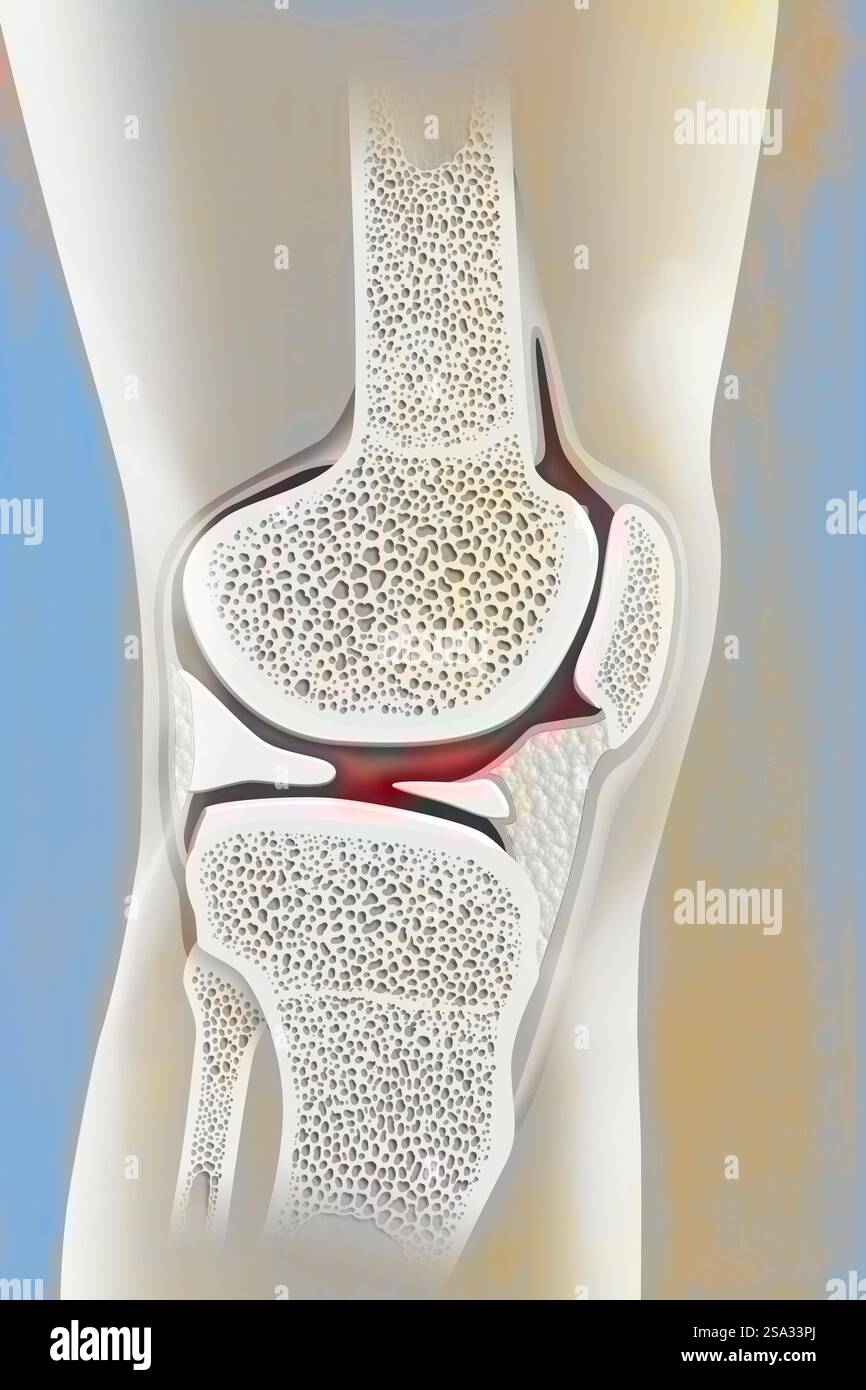

Coxofemoral joint and femoral neck. Hip drawing 016238 052 Stock Photohttps://www.alamy.com/image-license-details/?v=1https://www.alamy.com/coxofemoral-joint-and-femoral-neck-hip-drawing-016238-052-image642999011.html

Coxofemoral joint and femoral neck. Hip drawing 016238 052 Stock Photohttps://www.alamy.com/image-license-details/?v=1https://www.alamy.com/coxofemoral-joint-and-femoral-neck-hip-drawing-016238-052-image642999011.htmlRM2SA33PB–Coxofemoral joint and femoral neck. Hip drawing 016238 052